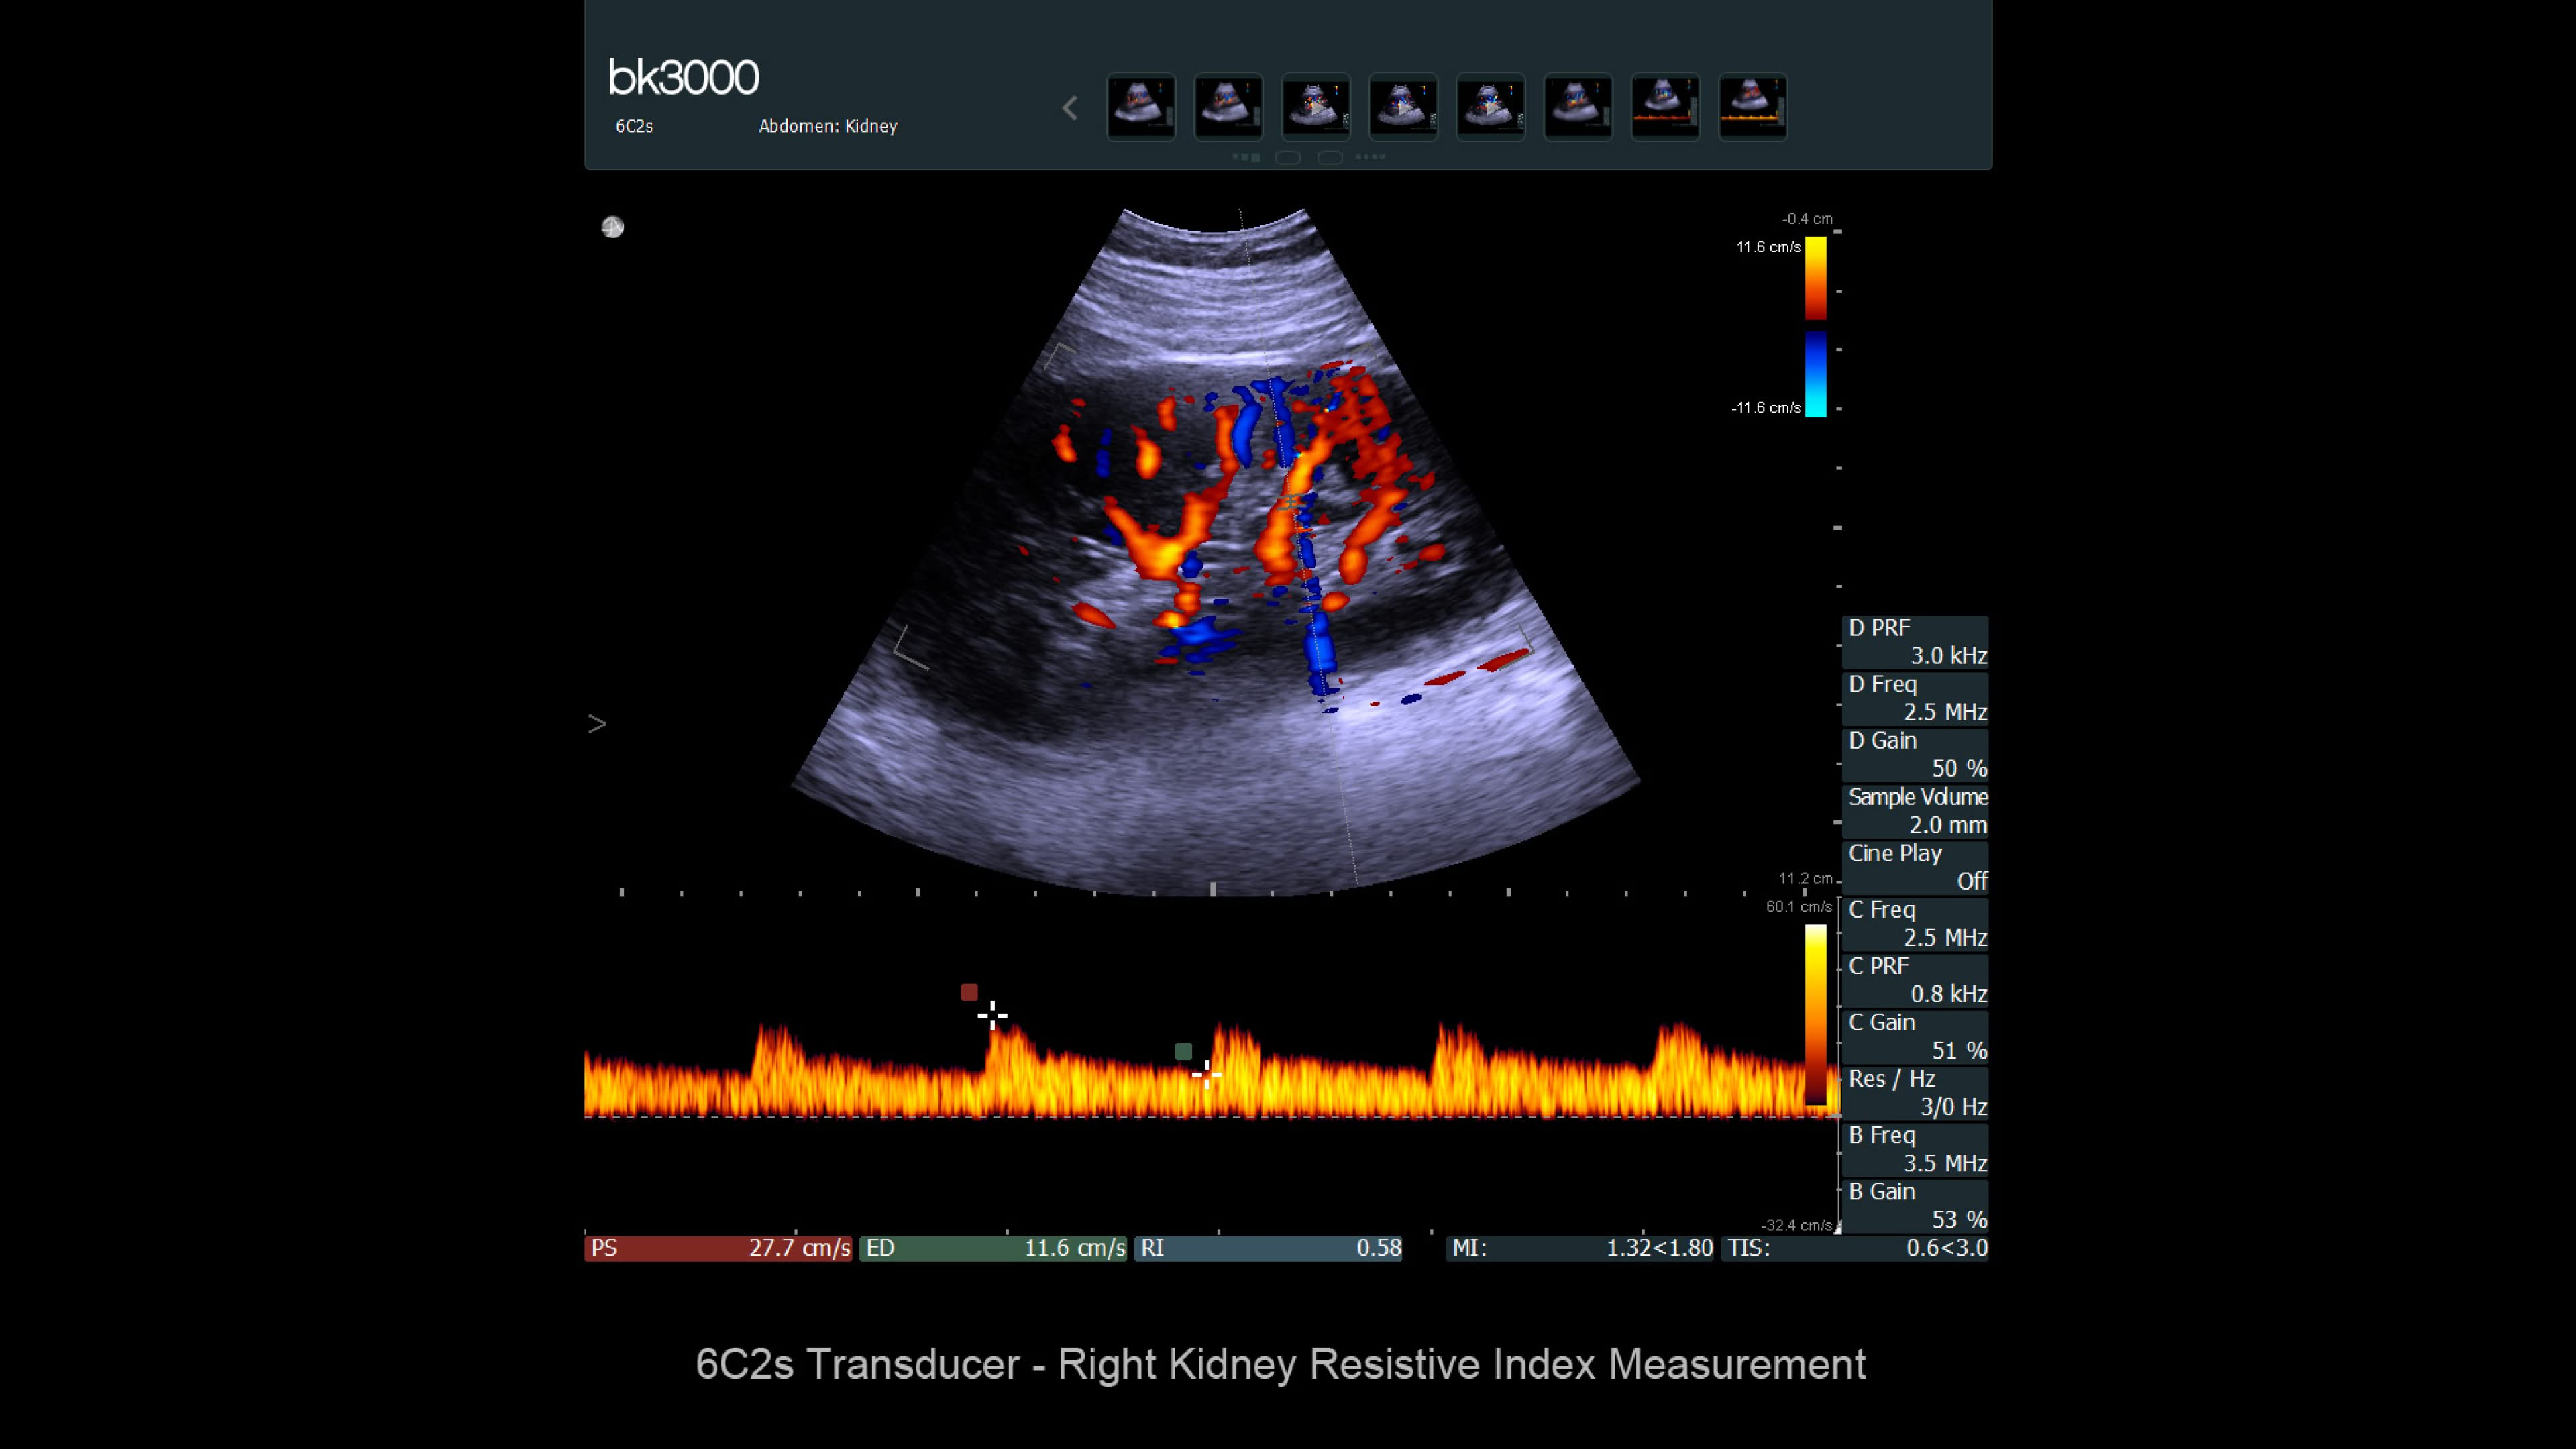

Ultrasound provides detailed information for kidney imaging, measurement, and biopsies. The bk3000 and bkSpecto systems help visualize fine anatomical details, see vascularization, measure blood flow, and locate kidney stones. The bkActiv, our flagship system, offers next-level imaging for prostate, renal, kidney, and bladder imaging, with sensitive Doppler for blood flow. Combined with sterilizable transducers, the bkActiv sets a new standard for surgical urology.